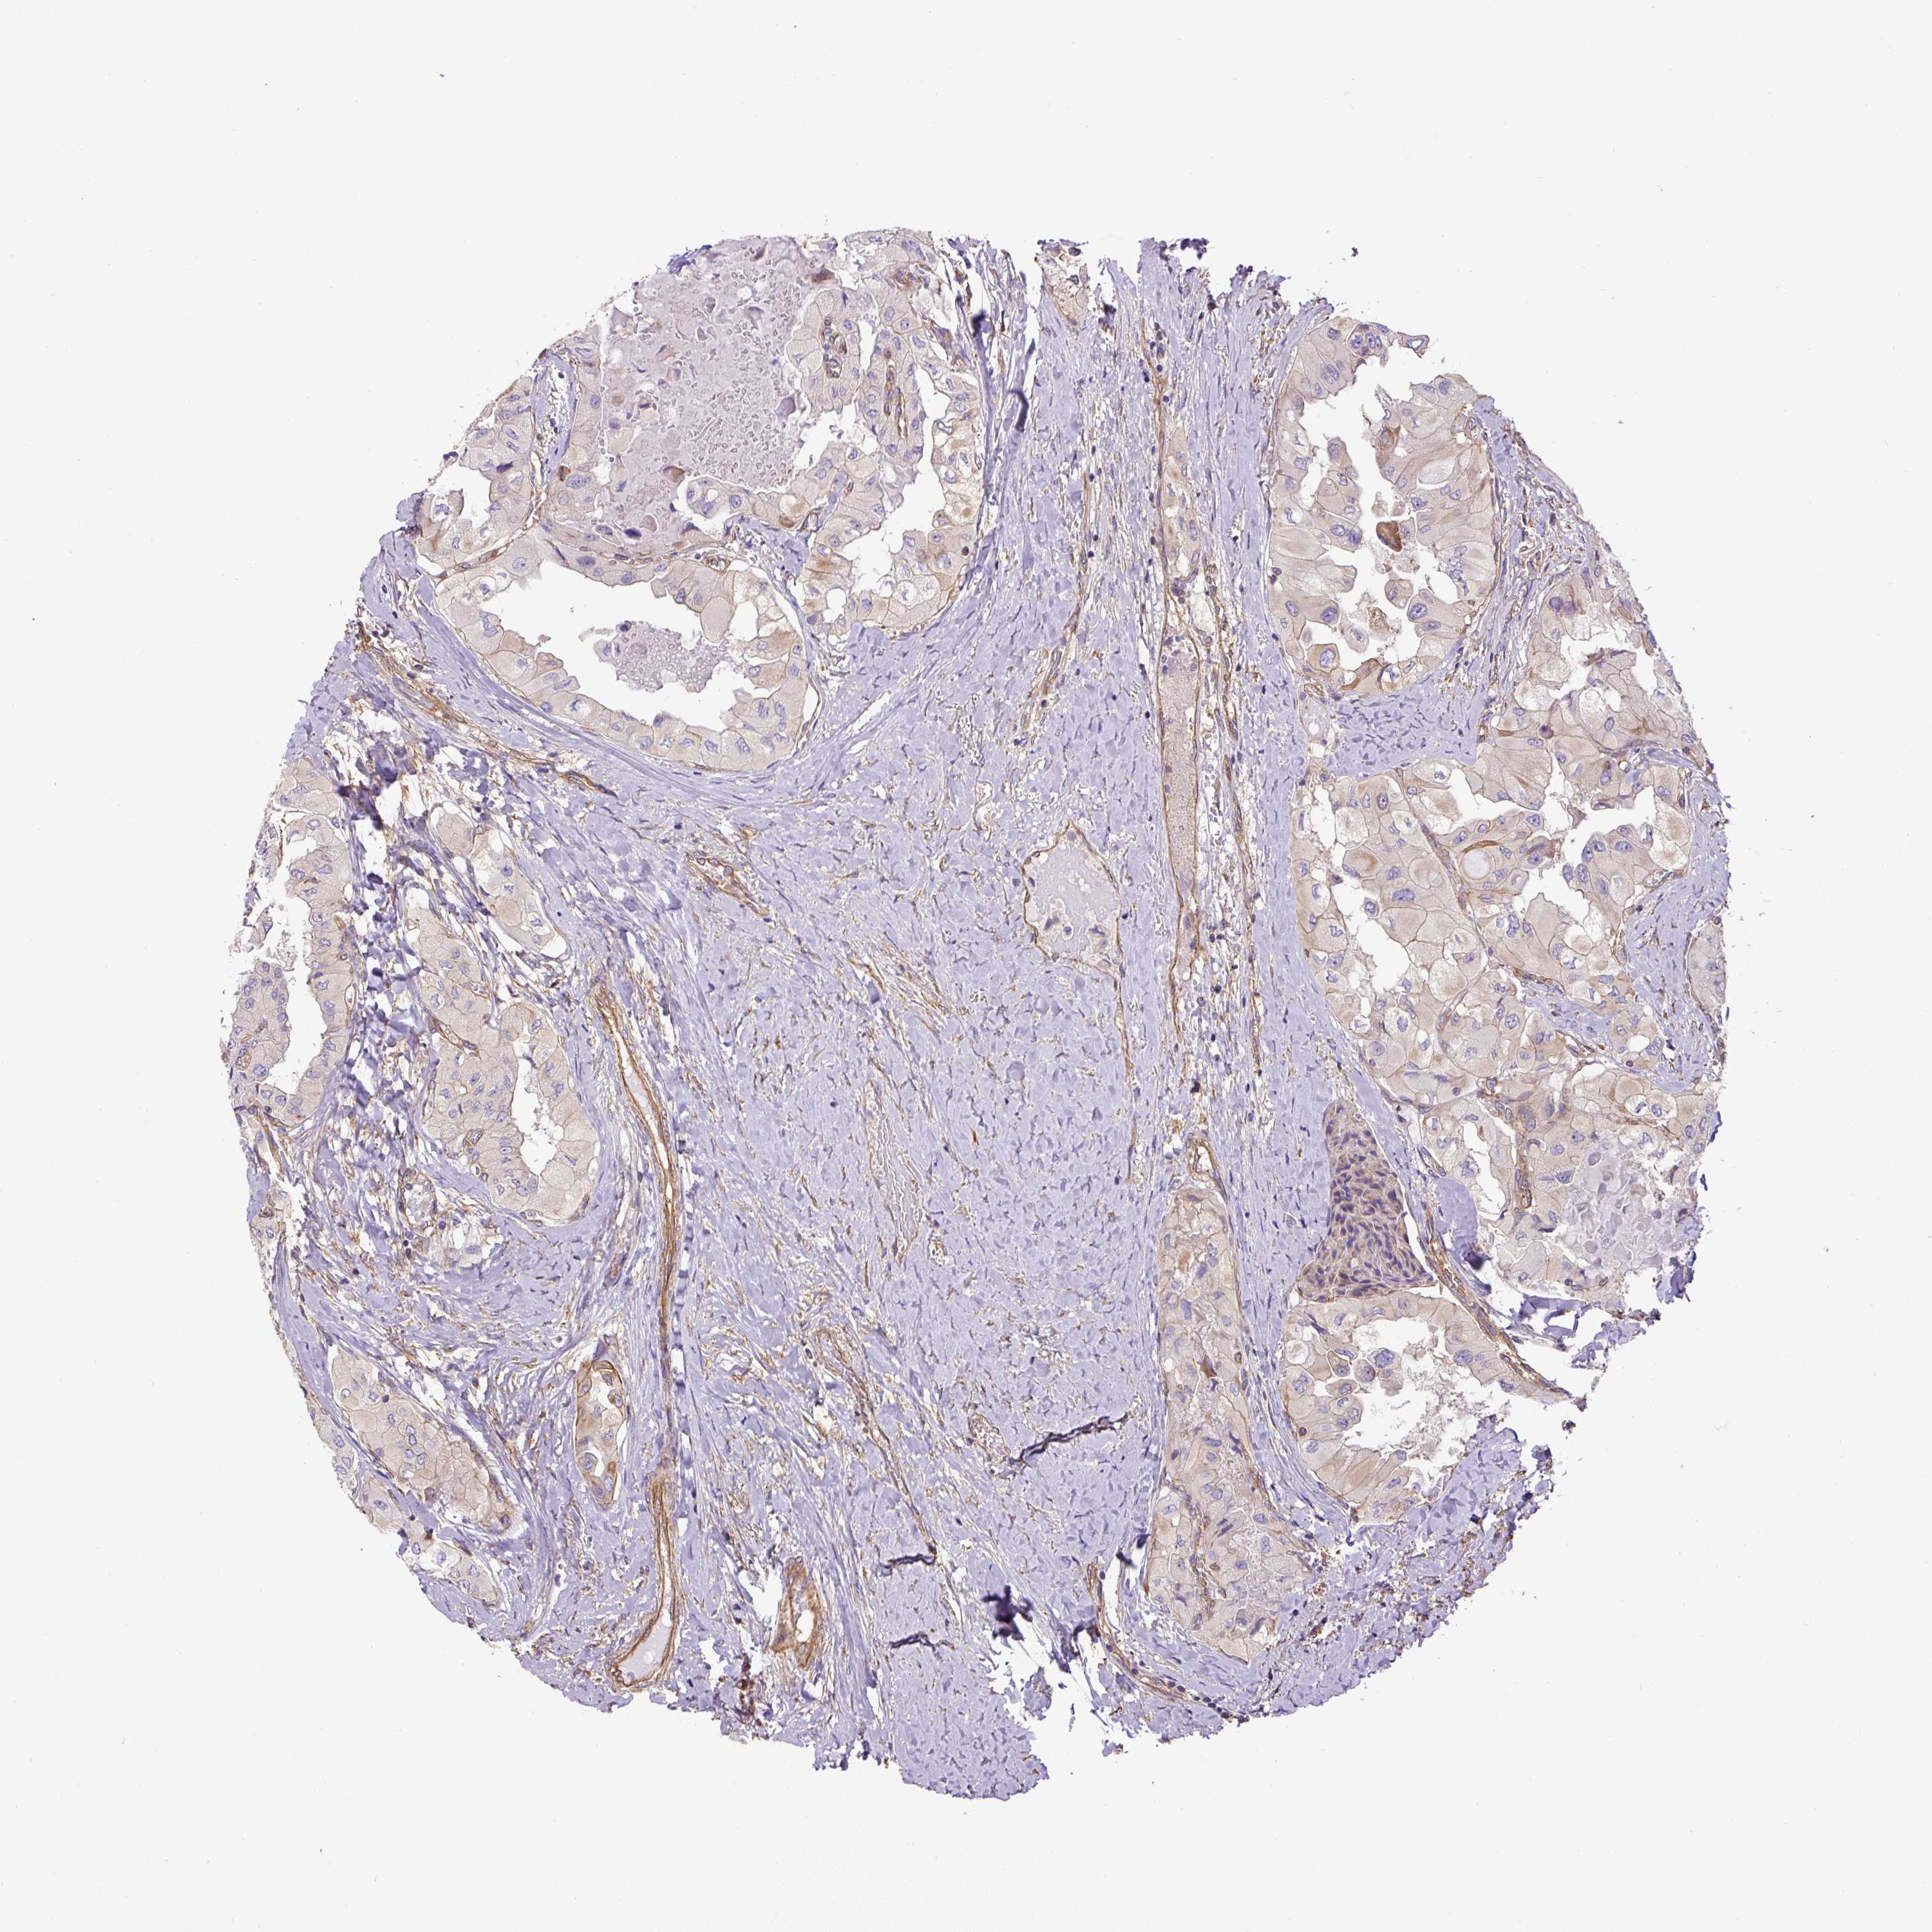

THYROID CANCER - Protein expressioni

A mouse-over function shows sample information and annotation data. Click on an image to view it in a full screen mode. Samples can be filtered based on level of antibody staining by selecting one or several of the following categories: high, medium, low and not detected. The assay and annotation is described here.

Note that samples used for immunohistochemistry by the Human Protein Atlas do not correspond to samples in the TCGA dataset.

Antibody stainingi

Antibody staining in the annotated cell types in the current human tissue is reported as not detected, low, medium, or high, based on conventional immunohistochemistry profiling in selected tissues. This score is based on the combination of the staining intensity and fraction of stained cells.

Each image is clickable and will lead to virtual microscopy that enables deeper exploration of all samples and also displays staining intensity scores, fraction scores and subcellular localization as well as patient and tissue information for each sample.

Antibody HPA034635

Antibody HPA069977

Antibody HPA071875

Antibody CAB009108

Staining

High

Medium

Low

Not detected

Intensity

Strong

Moderate

Weak

Negative

Quantity

>75%

75%-25%

<25%

None

Location

Nuclear

Cytoplasmic/membranous

Cytoplasmic/membranous,nuclear

Papillary adenocarcinoma, NOS

Follicular adenoma carcinoma, NOS